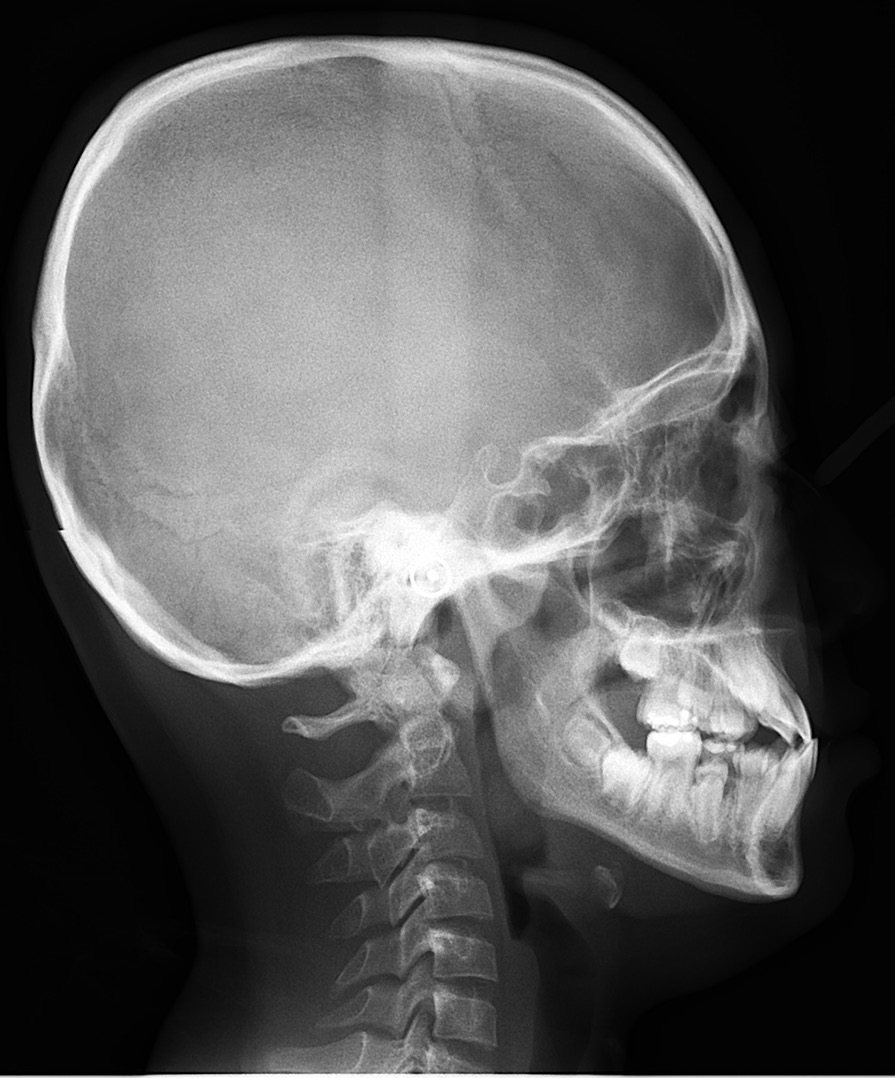

首先要观察下颌骨形态。如果是高角,这种反颌难做,需要很多时间。如果是均角或者低角,矫治效果好而且稳定,不容易复发。

如果是上颌后缩,这种反颌也相对好做一些。但是如果是下颌前突,这种情况很差,下颌骨可能会随着生长越来越前突,反颌可能会加重。

头影测量中有一个方法简单有效——从 N 点(鼻根点)做眶耳平面的垂线,即 Mcnamara 线,上颌骨 A 点(上齿槽座点)距离该垂线的正常距离,0mm(儿童),1~2mm(成人);下颌骨 Pog 点(颏前点)距离该垂线的正常距离,- 6mm(儿童),- 2mm(成人)。

上颌后缩情况

下颌前突情况